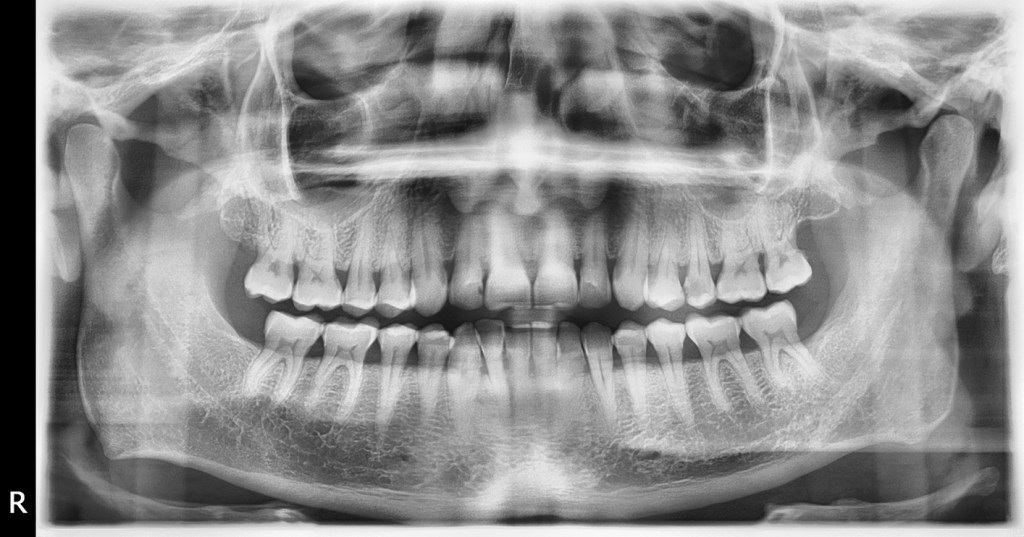

Debido a su capacidad para penetrar ciertos materiales, los rayos X se emplean para identificar grietas en algunas estructuras o para buscar defectos internos en piezas. También se utiliza en los hospitales y en los dentistas para crear imágenes de rayos X de huesos y dientes.